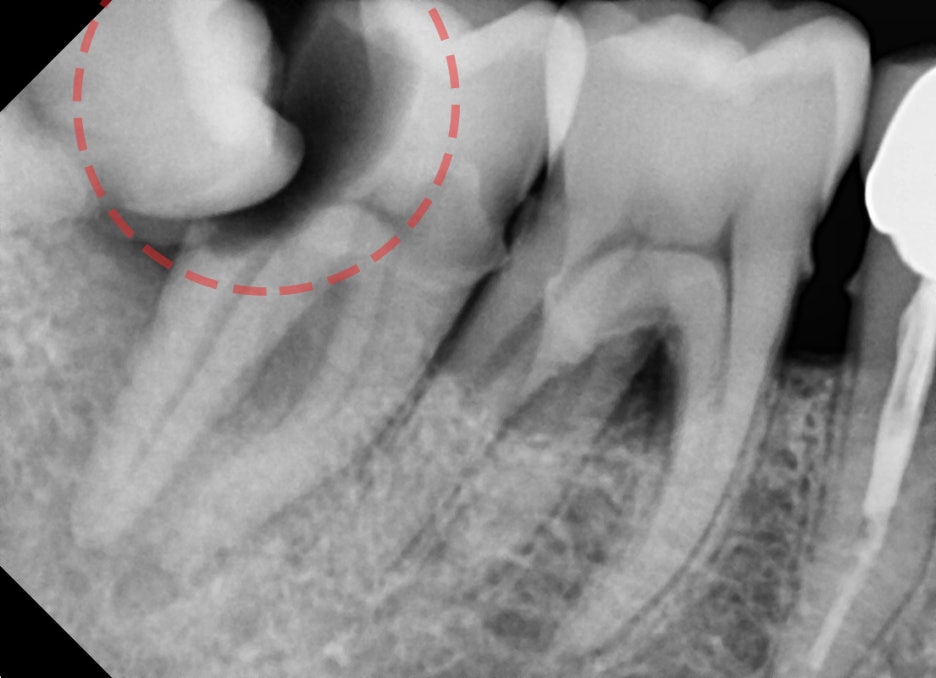

조금 더 해상도 높은 엑스레이를 보여드릴게요.

어머나.. 바로 앞에 있는 제 2대구치의 치관 1/3 가량이 썩어있습니다.

신경치료도 되어있지 않은 곳이기 때문에 이미 상당한 통증을 느끼고 계셨던 터라

하루 빨리 치료를 해야 되는 상황이였습니다.

근데.. 이렇게 많이 썩은 치아를 살릴 수 있을까요?

아뇨.. 살린다 한들 예후가 그리 좋지 않기 때문에 오히려 상황이 더 악화되는 것을

막는 예방차원에서 임플란트 수술을 권장드렸었습니다.